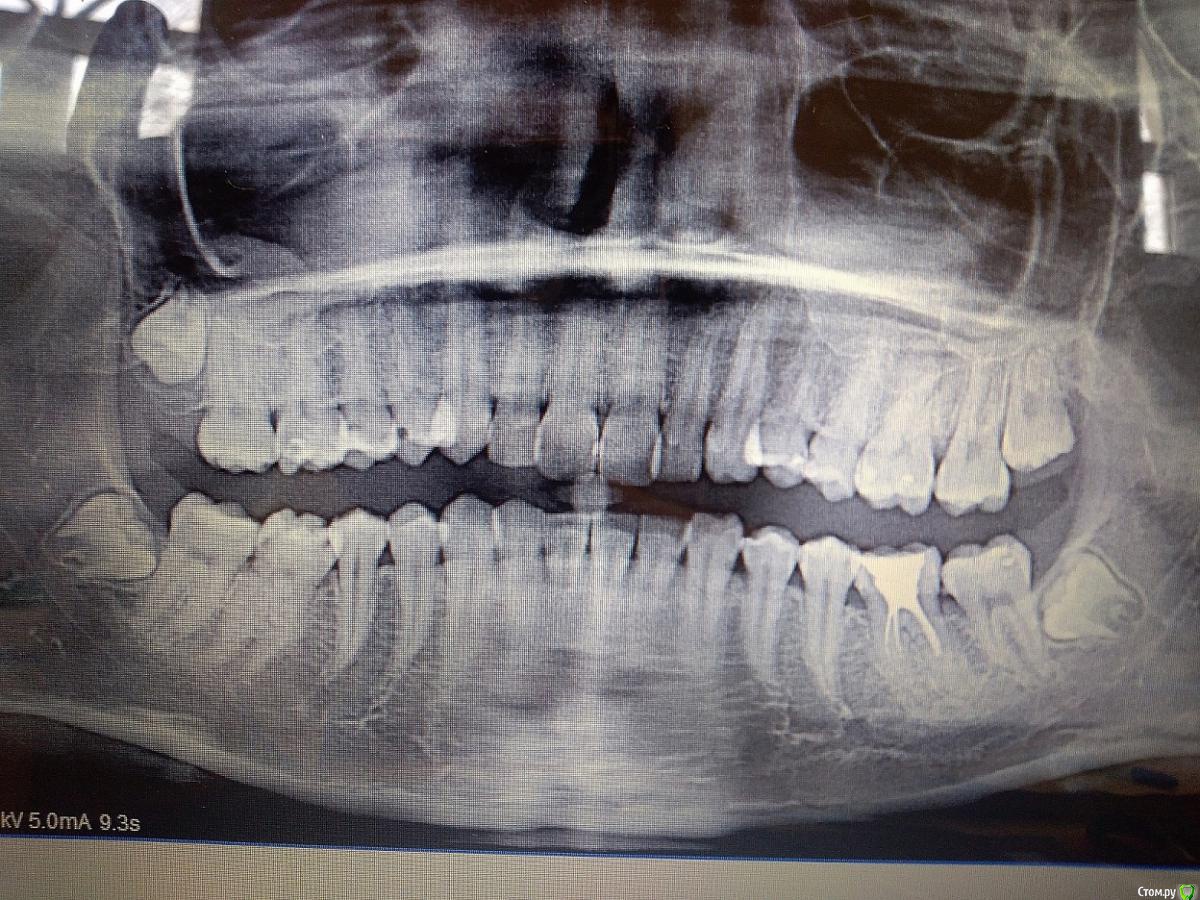

Гузель77 Опубликовано 22 января, 2019 Поделиться Опубликовано 22 января, 2019 (изменено) Здравствуйте! Буду благодарна за ответы. Очень сильно переживаю за зуб, Мне всего 21 год. Когда пришла лечить кариес, пожаловалась на странные ощущения в корнях переднего зуба, это даже болью сложно назвать, просто странные ощущения.(когда это началось, точно не помню, но мес. 3 точно наверное). И десна сзади между передними зубами иногда воспаляется, когда ем хрустящую пищу, например от хрустящего лаваша шаурмы или выпечки в духовке, на след день проходит. Лет 5 назад левый передний зуб пломбировали. Стоматолог оправила на снимок переднего зуба. Он прилагается. Скачала, что немного есть разряжение костной ткани и сказала прийти, если будет болеть. Назначила Найз, 3 дня по три раза в день. Весной 18-го года лечила гингивит или пародонтит (точно не определили), очень сильно кровоточили зубы и поднялись немного десна, у некоторых особенно. Тогда назначили антибактериальные (метронидазол), полоскание хлоргексидином и гели. (это на всякий случай, может имеет какое-то значение). Сейчас вроде не кровоточат, могут кровоточить немного, когда очень усердно чищу зубы. Тогда мне тоже сделали снимок, он тоже прилагается. 1-ый снимок (сегодня)2-ой снимок (весна 18-го года) Вопрос: может ли это как-то само собой пройти или остаться на этой стадии, и не привести ни к чему серьезному? Что делать с этой проблемой? Может какие-то полоскания, лекарства (аллергии ни на что нет). На сколько серьезна моя ситуация? Изменено 22 января, 2019 пользователем Гузель77 Ссылка на комментарий

kramer Опубликовано 22 января, 2019 Поделиться Опубликовано 22 января, 2019 Здравствуйте. Не вижу никакого разрежения. 1 Ссылка на комментарий